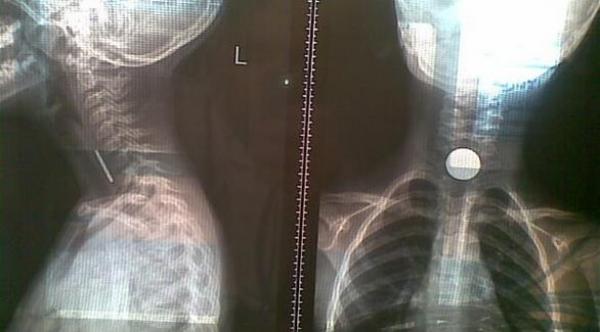

سعال طفلة يكشف عن عملة معدنية عالقة في حنجرتها